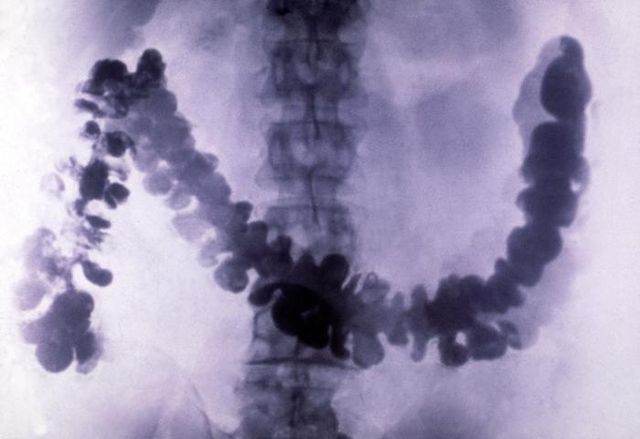

The gastric antrum appears “gray,” not black as a purely air-filled structure would appear. Most of the x-rays, but not all, pass through the antrum, partially exposing the film. Because barium absorbs more x-rays than air, the gastric fundus appears “white.” In this radiograph, the anteriorly located gastric antrum is filled with air and is also “etched in white” by a thin layer of barium. The gastric fundus is posterior to the gastric antrum barium falls into the gastric fundus when the patient lies in a supine position. This image was obtained with the patient recumbent, back against the fluoroscopic tabletop (a supine radiograph). The heavy barium falls to the lowest or most “dependent” portion of the stomach. The relatively exposed areas of the film appear as shades of black the relatively unexposed areas of the film appear as shades of white. X-rays easily pass through GI structures filled with air and expose the film. X-rays passing through barium are blocked and do not reach the film. 15-2, whereas the antrum appears gray?īarium sulfate absorbs and scatters x-rays, but air does not.

Rubesin MD, in Radiology Secrets Plus (Third Edition), 2011 6 Why does the gastric fundus appear white in Fig.